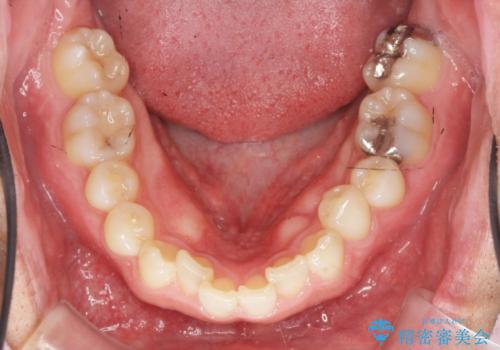

2級ディープバイト 遠心移動を伴うマウスピース矯正

- 前歯のがたつきを改善したい、と矯正治療を希望され来院されました。

・深い噛み合わせ(ディープバイト) ・2級性の咬合関係(上顎前突)・前歯のがたつき

以上のような歯並びの問題をマウスピース矯正インビザライン・カリエール・マイクロインプラント・部分ワイヤー矯正

を用いて改善していきます。